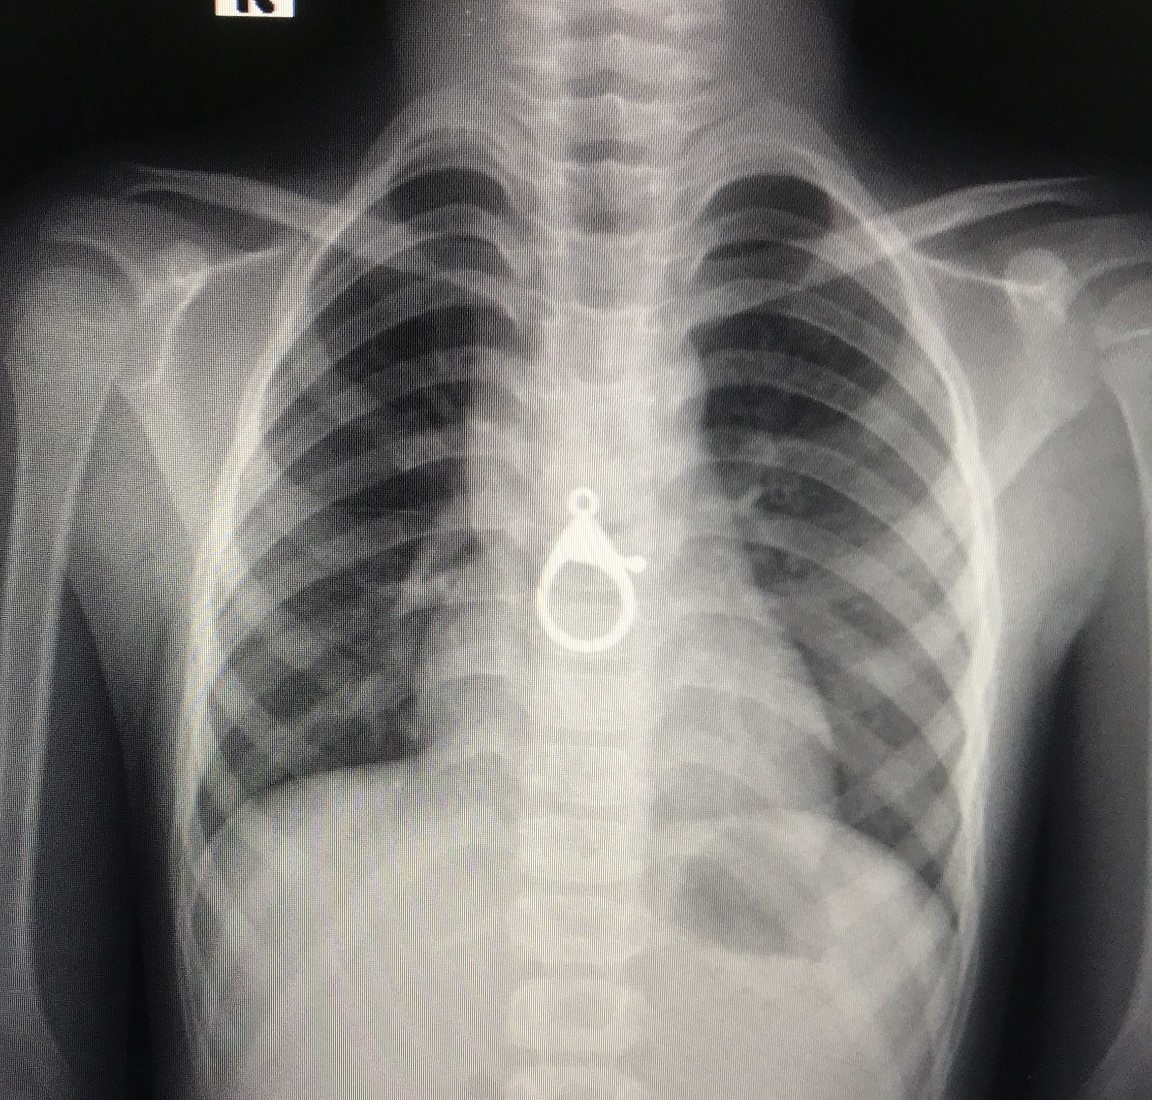

Dị vật được bác sĩ phát hiện trong ngực bé trai. Ảnh: Bệnh viện cung cấp.

Bệnh nhi là T.Đ.H. (6 tuổi, ngụ xã Tam Hòa, huyện Núi Thành, Quảng Nam), nhập viện chiều 13/8, trong tình trạng tức ngực, khó thở.

Người nhà cho biết trong lúc chơi đùa, bé H. ngậm móc khóa và vô tình nuốt xuống họng.

Qua thăm khám, chụp X-quang, bác sĩ phát hiện dị vật hình móc khóa ở trong vùng ngực bé H. Bệnh nhi được chuyển vào khoa Gây mê - Phẫu thuật. Bác sĩ Tiên chỉ định nội soi và lấy ra dị vật. Bệnh nhân đang dần hồi phục.